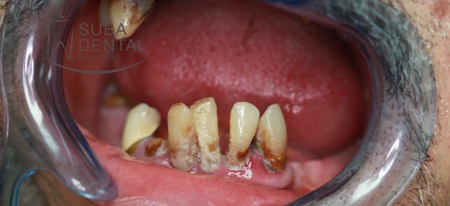

Neglected chronic periodontal disease

The dentist’s primary goal is the conservation of teeth with professional tartar removal and the instruction of patients on thorough brushing techniques. Sadly, everyday experience shows that due to smoking and the complete neglect of hygiene, teeth will decay beyond repair. The problem can be addressed by the extraction of the teeth and cleansing inflamed tissues, but the question of “what next?” also has to be dealt with. Everyone wants to have their lost teeth replaced, and most people prefer a fixed solution to a removable one. When extracting focal teeth, a dentist always has to bear in mind bone decay resulting from the inflammatory processes in the region at hand. On such occasions the dentist will have to consider the extent of bone decay and whether sufficient bone mass remains after tooth extraction for an implant surgery to be viable and whether the regeneration of bone will be adequate for implantation. The greater the extent of neglect or the longer an inflammation goes untreated, the greater the risk that the bone mass having perished will no longer sustain a “plain” dental implantation, a bone graft will also be necessary. Following tooth extractions and healing (3 months on average) implant surgery can be performed. Prior to the intervention, for the thorough planning of the site and size of the implants a CBCT (Cone beam computed tomography) is performed at all times.

Panoramic radiograph of chronic dental foci, teeth affected by periodontal disease, and root remains. All teeth had to be extracted